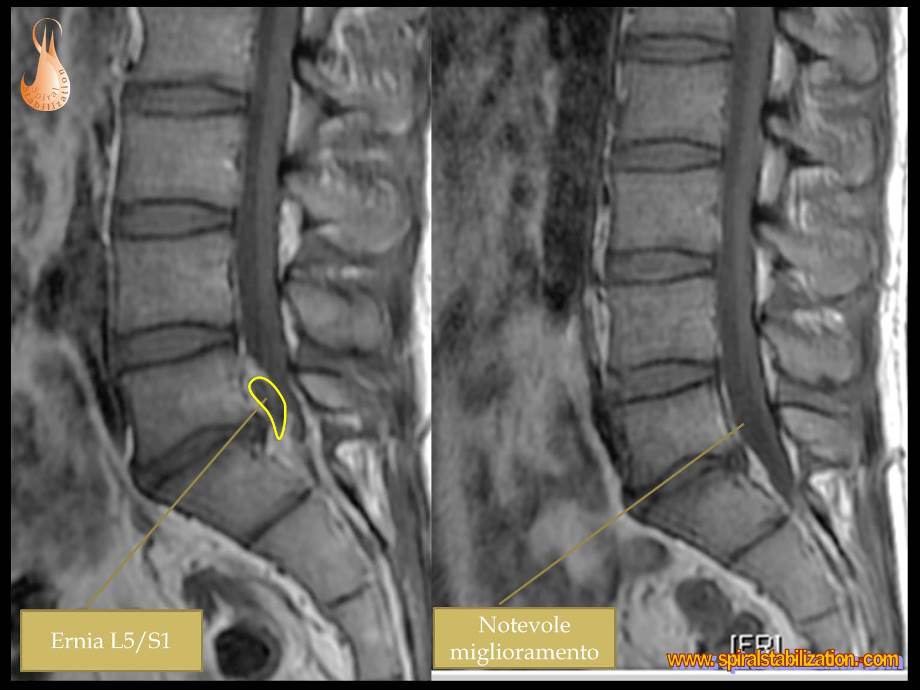

3 - Ernia L5/S1

B - 1 - 1 - 3

Ernia del disco L5/S1